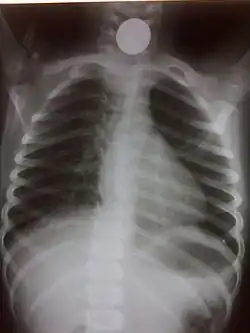

A coin seen on AP CXR in the esophagus -